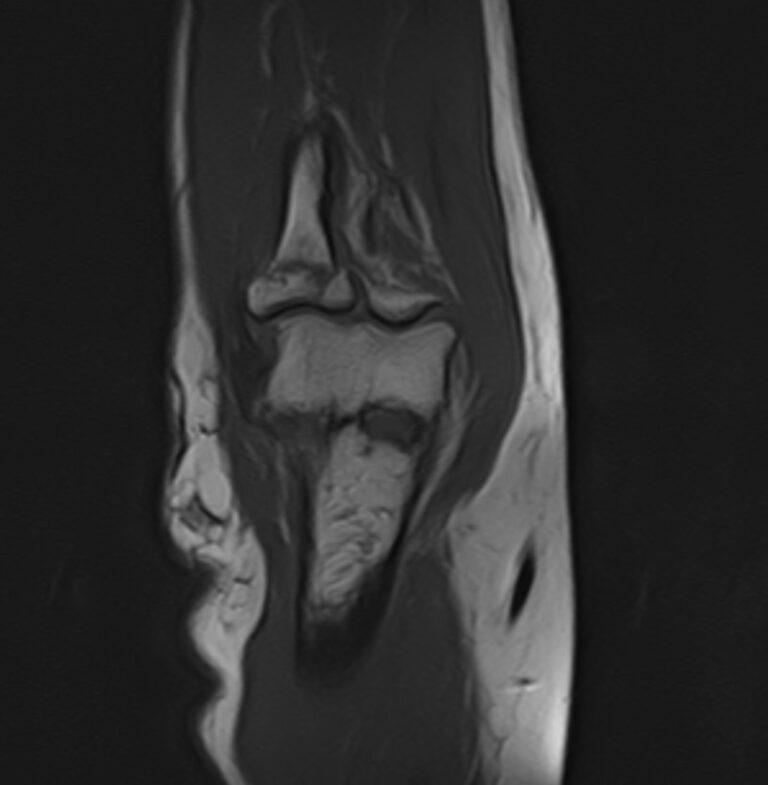

Локтевой сустав представляет собой подвижное сочленение плечевой кости с лучевой и локтевой костями предплечья. Сочленение имеет сложное строение и состоит из трех суставов, заключенных в одной составной капсуле. Сустав выполняет несколько видов движений и испытывает интенсивные нагрузки, поэтому часто подвергается травматизации и развитию различных заболеваний, в том числе, воспалительных и дегенеративно-дистрофических. Болевой синдром в локтевом суставе, который возникает при многих патологиях, требует проведения дифференциальной диагностики с помощью высокоточных методов обследования.

Магнитно-резонансная томография является наиболее информативным методом диагностической визуализации всех структур локтевого сустава, включая костные структуры, связки, сухожилия, прилегающие мягкие ткани. По сравнению с другими методами обследования, такими как УЗИ, рентгенография и компьютерная томография, МРТ позволяет получить наибольшую информацию о патологических процессах в суставе и окружающих тканях, поставить точный диагноз и определить тактику лечения. При этом МР томография не оказывает вредного воздействия на организм, так как технология процесса не предусматривает использование рентгеновского излучения.

В клинике «Доступная медицина» проводится МРТ локтевого сустава на современном томографе закрытого типа TOSHIBA VANTAGE TITAN 1,5 Тесла. Благодаря высокой мощности магнитного поля устройство при сканировании выявляет даже минимальные очаги поражения сустава и на основе полученных данных проводит построение 3D-модели. Кроме того, для увеличения информативности МРТ в некоторых случаях применяется введение контрастного вещества, содержащего в своем составе металл гадолиний.

Что показывает МРТ локтевого сустава

При глубинном и тщательном исследовании, МРТ обеспечивает легкое обнаружение ряда проблем, которые достаточно сложно диагностировать визуально, посредством анализов или других методик диагностики. Иногда это сделать вовсе невозможно. Без оперативного вмешательства, с помощью МРТ локтевого сустава можно определить: